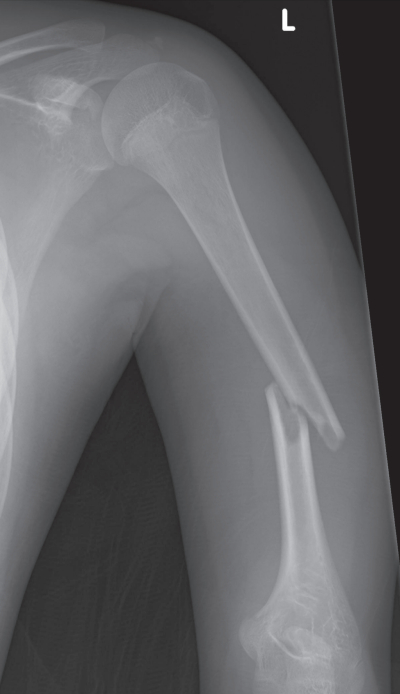

身長 133 cm、体重 28 kg。体温 36.5 ℃。左上腕中央部に腫脹を認める。左手関節の背屈ができず、左手背に感覚鈍麻を認める。左上腕骨エックス線写真を別に示す。

障害されている神経はどれか。